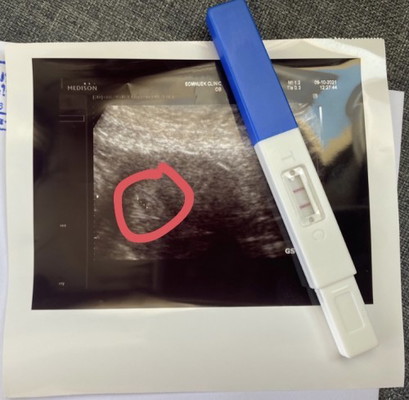

ท้อง5สัปดาห์5วัน

สวัสดีค่ะแม่ๆทุกท่าน มีเรื่องจะรบกวนสอบถามค่ะ วันนี้ไปอัลตราซาวด์มา ถ้านับอายุครรภ์จากวันที่มีประเดือนวันแรกของครั้งสุดท้าย ได้5วีค5วัน แต่อัลตราซาวด์ไม่เจอตัวอ่อน อัลตราซาวด์ทางหน้าท้องนะคะ เจอแต่ถุงการตั้งครรภเล็กมากๆ แบบนี้ปกติมั้ย แถมยังไม่มีอาการคลื่นไส้ คัดเต้า มีแค่หิวบ่อยกว่าปกติเท่านั้น #ขอบคุณล่วงหน้านะคะ #ใครมีประสบการณ์ รบกวนด้วยนะคะ